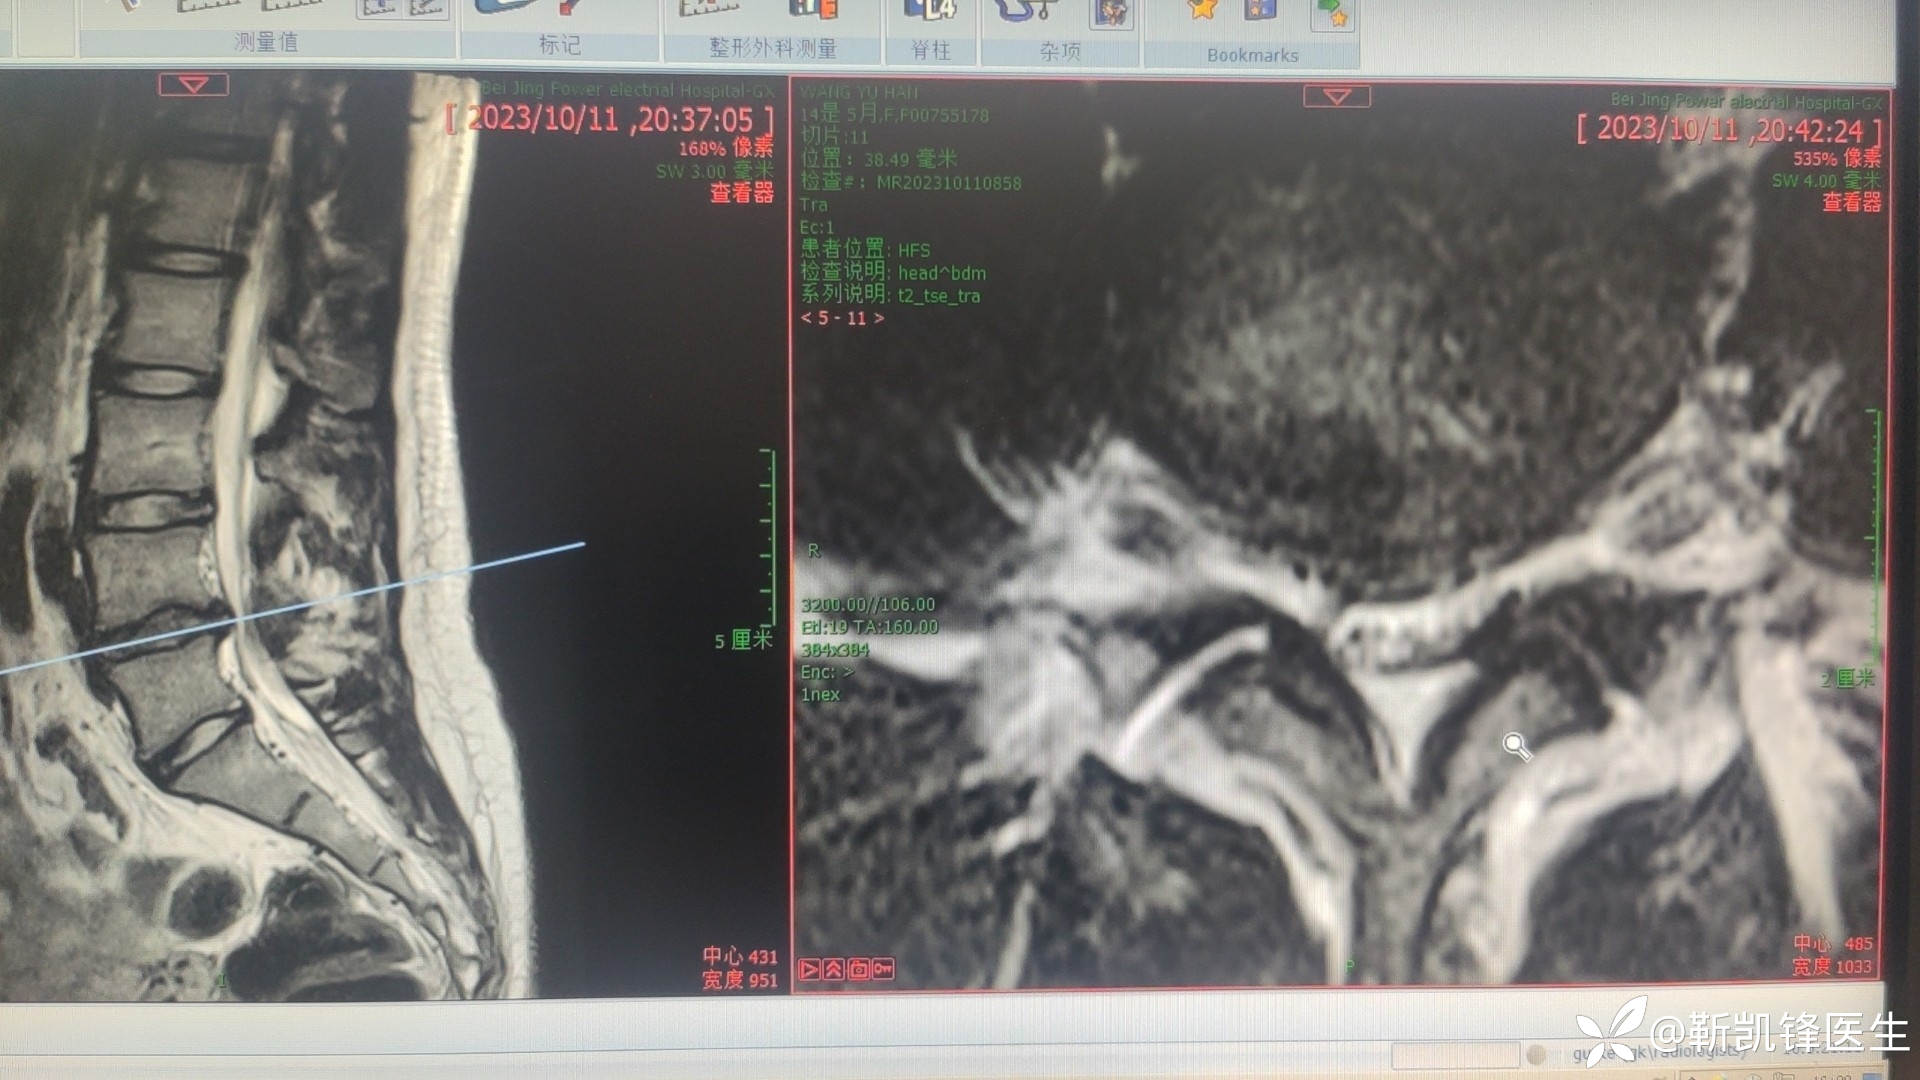

病例14岁青少年腰椎间盘突出症

门诊病人,14岁,学生,腰痛伴有双侧腿疼腿麻三个月,弯腰咳嗽导致腿痛腿麻加重,影响生活和学习。其余查体门诊未检查。请各位大佬指导,下一步治疗,继续保守治疗还是孔镜?